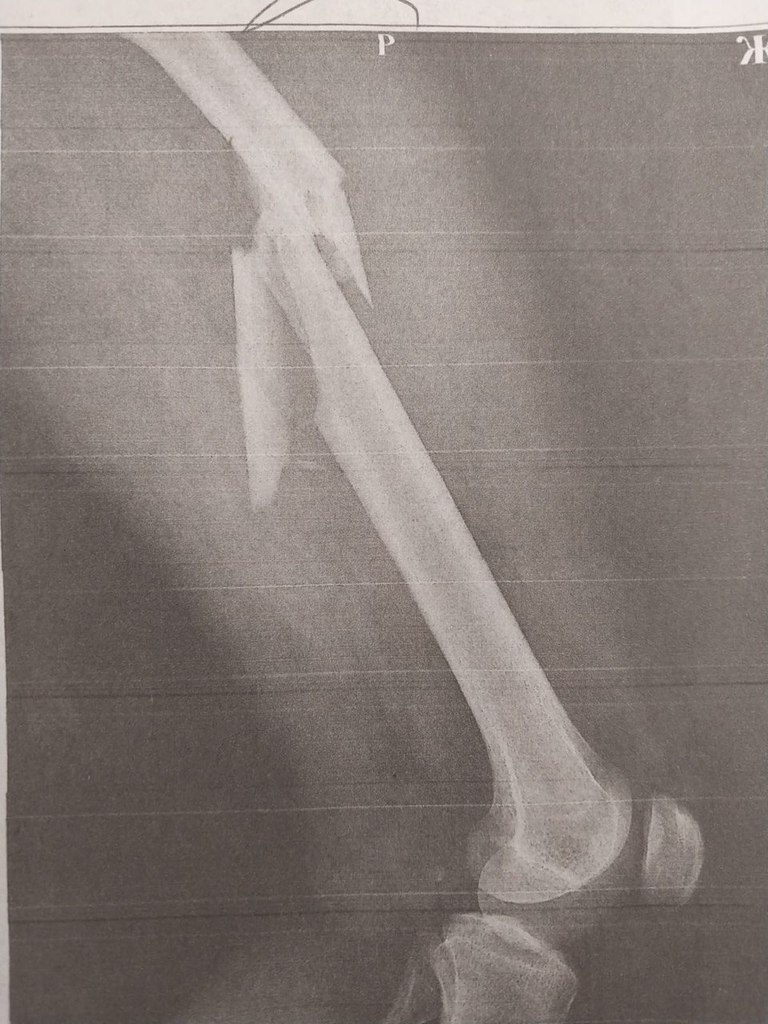

Травматологи «Липецк- Мед» буквально по кусочкам собрали бедренную кость пациента. Провели остеосинтез левого бедра.